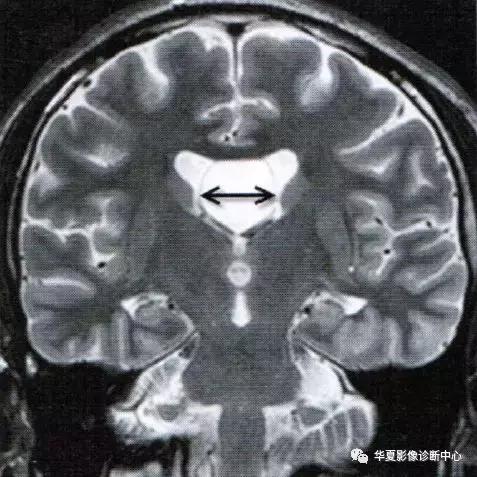

上图为透明隔囊肿

透明隔囊肿表现为透明隔两侧壁弯曲甚至膨隆,失去正常平行状态,且侧壁间距>10mm